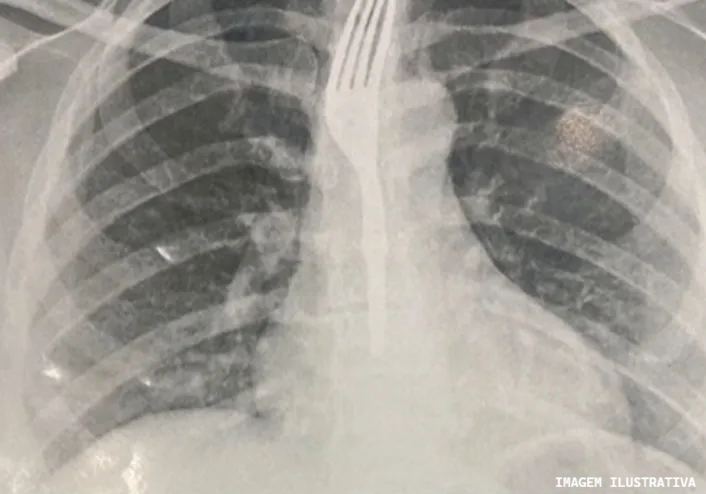

Um caso inusitado foi registrado em Guanambi, uma mulher necessitou de atendimento médico urgente após engolir um garfo enquanto comia uma sobremesa. A paciente deu entrada na emergência do Hospital Geral de Guanambi (HGG) por volta das 13h30 da última sexta-feira (26) e os exames revelaram o objeto alojado no esôfago, em posição de risco.

Por conta da gravidade do caso, a equipe médica resolveu transferir a paciente para Vitória da Conquista, para receber um atendimento especializado. Seu estado de saúde ainda não foi divulgado. Especialistas alertam: não tentar remover o objeto manualmente, nem oferecer alimentos ou líquidos à vítima. A recomendação é buscar atendimento médico imediato e, em caso de dificuldade respiratória, acionar o Samu (192) ou dirigir-se ao pronto-socorro mais próximo.